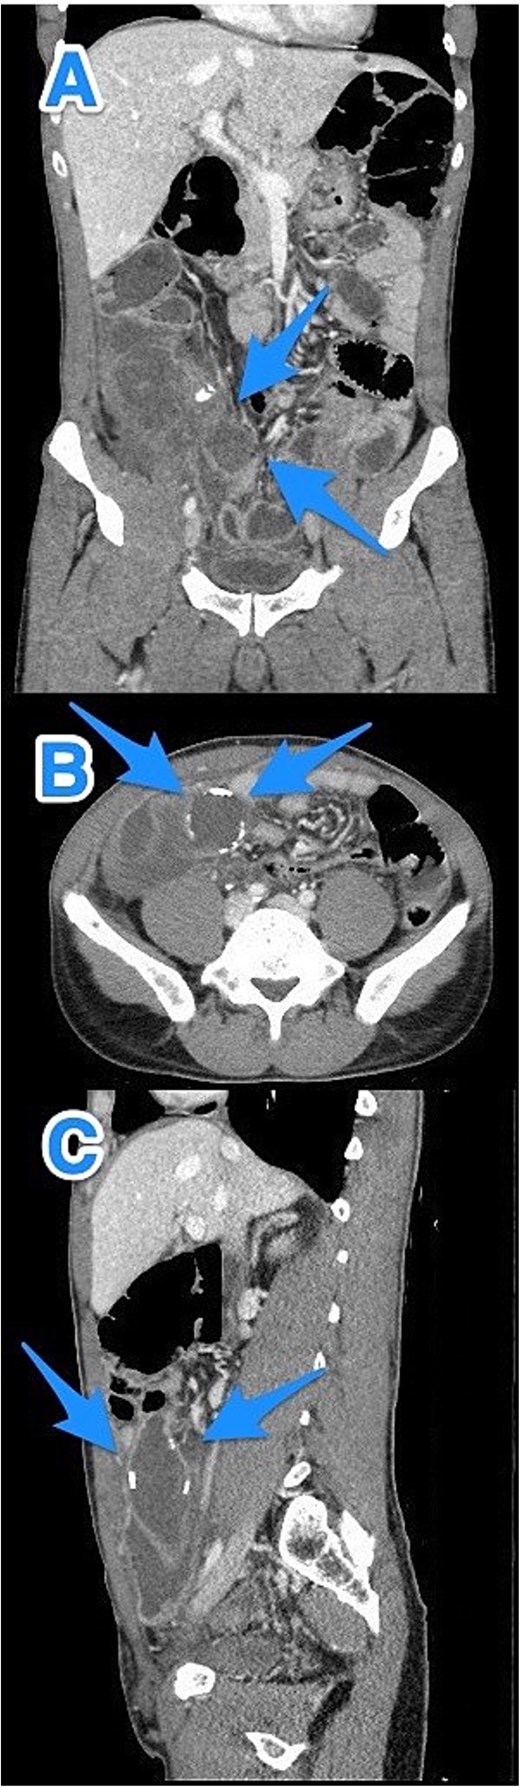

A 46-year-old male with a history of leukemia treated with chemotherapy and primary infertility presented with right lower quadrant abdominal pain of less than one day's duration. He reported associated nausea but no vomiting, changes in bowel habits, or fever. On systemic evaluation, the patient demonstrated stable vital signs, full consciousness, and alertness, with no evidence of severe pain. Abdominal examination revealed rebound tenderness in the RLQ, but the abdomen was otherwise soft, with no tenderness upon palpation of other regions. Laboratory investigations were within normal limits. Abdominal CT with contrast revealed evidence of appendiceal perforation. The liver showed moderate to severe steatosis, but no other remarkable abnormalities were detected (Fig. 5). Due to the perforation near the base of the appendix, a right hemicolectomy was performed. Histopathological examination of the appendix confirmed the diagnosis of LAMN (Fig. 6). The tumor extended to the visceral peritoneum through the perforation site, but there was no evidence of lymphatic, vascular, or perineural invasion. Four reactive lymph nodes were negative for tumor infiltration, and the pathologic TNM staging was pT4, pN0. The specimen also contained acellular mucin evacuated during the surgery. Postoperative recovery was uneventful, and the patient was later transferred to a higher center for comprehensive assessment and continued care.

CT abdomen and pelvis with contrast: (A) coronal, (B) axial, and (C) sagittal views reveal an appendix measuring 22 cm in the right iliac fossa, with edematous wall thickening, minimal surrounding fat stranding, and an adjacent fluid collection measuring 3.3 × 1.8 × 8.5 cm, consistent with a perforated appendix (arrows).